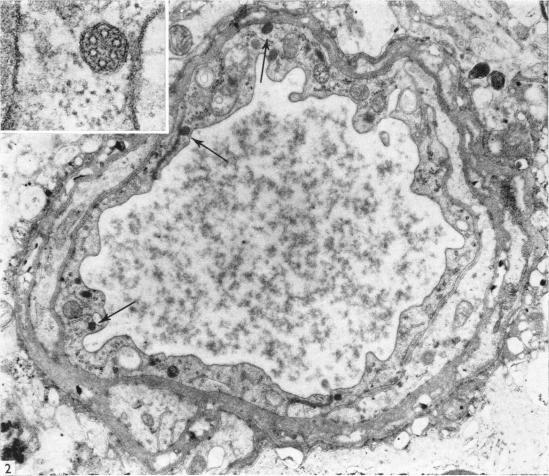

Endothelial microtubular bodies in human brain capillaries and venules.

J Anat. 1974 Nov;118(Pt 2):205-9.